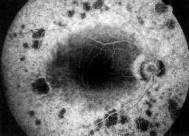

B 眼科での検査の所見

眼底 網膜の血管が細くなる。網膜に黒い色素沈着がみられます。白い点が認められる

こともあります。上左写真の黒い点が色素沈着です。

蛍光眼底撮影 眼底の血管撮影です。網膜色素上皮の萎縮や網膜の血管が細くなってい

るのがわかります。右写真の周辺部で黒く抜けて見えるところは色素上皮が萎縮

して下が見えている部分です。